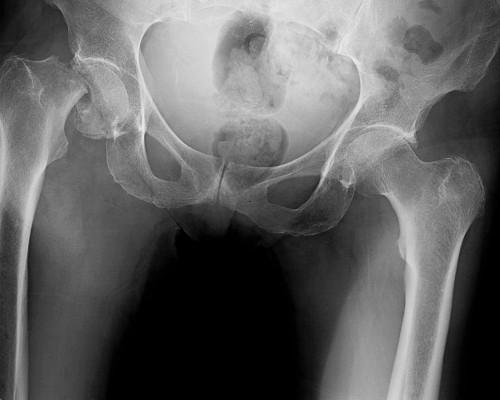

Hip Arthritis

Stiffness isn’t just a sign of “getting older”; it could be arthritis wearing down your joint. Dr. Mehta helps relieve chronic pain through surgical and non-surgical solutions when conservative care isn’t enough.